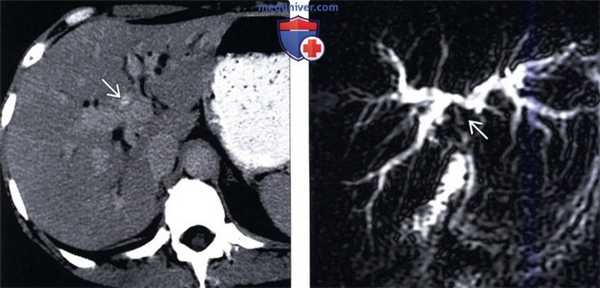

(Слева) На КТ в артериальной фазе контрастного усиления у мужчины 35 лет с пальпируемым в эпигастрии образованием визуализируется большое объемное образование с неровными контурами, в котором находятся крупные, ветвящиеся неопластические кровеносные сосуды.

(Справа) На более каудальном срезе у этого же пациента определяется неравномерно повышенное накопление контраста в образовании, визуализируется гиподенсный центральный рубец. Обратите внимание на крупную артерию, несущую кровь по направлению к образованию. (Слева) На КТ в венозной фазе контрастного усиления у этого же пациента визуализируется образование с неровными контурами, наличием капсулы, неравномерно накапливающее контраст, что позволяет отличить опухоль от ОНГ.

(Справа) На более каудальном срезе в венозной фазе контрастного усиления у этого же пациента вновь визуализируется образование, неравномерно накопившее контраст. (Слева) На КТ в отсроченной фазе контрастного усиления у этого же пациента визуализируются участки опухоли, длительно удерживающие контраст и становящиеся гиперденсными по отношению к печени, что является признаком наличия фиброзной стромы (характерная особенность фиброламеллярного рака).

(Справа) На корональной КТ у этого же пациента визуализируется образование: с признаками, характерными для ФЛР (большое, гиперваскулярное образование неоднородной структуры с крупным рубцом в центре, обнаруживаемое при отсутствии клинических или лучевых признаков цирроза или хронического заболевания печени). (Слева) Фиброламеллярный рак печени обычно выглядит как узел дольчатой структуры с центральным рубцом. Обратите также внимание на отсутствие признаков цирроза со стороны печени. (J. Misdraji, MD).